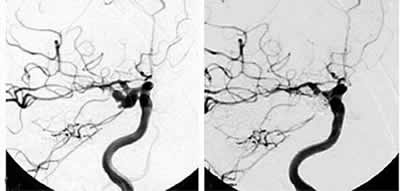

本报讯 一项由美国、加拿大和欧洲61个医疗单位协作完成的前瞻性研究显示,并非所有尚未破裂的脑动脉瘤都需要治疗。(Lancet 2003362∶90103)

该研究共纳入4060例未破裂脑动脉瘤病人。其中,1917例病人做了开颅修补术,451例病人接受了血管内介入治疗,1692例病人未进行治疗。随访期为5年。

以往无动脉瘤破裂史的前循环动脉瘤病人,5年累积破裂率分别为:直径<7 mm者为0;7~12 mm者为2.6%;13~24 mm者为14.5%;≥25 mm者为40%。后循环动脉瘤的相应值分别为:2.5%、14.5%、18.4%和50%。手术或血管内介入治疗的危险常常等于或超过上述未治疗病人的破裂率。